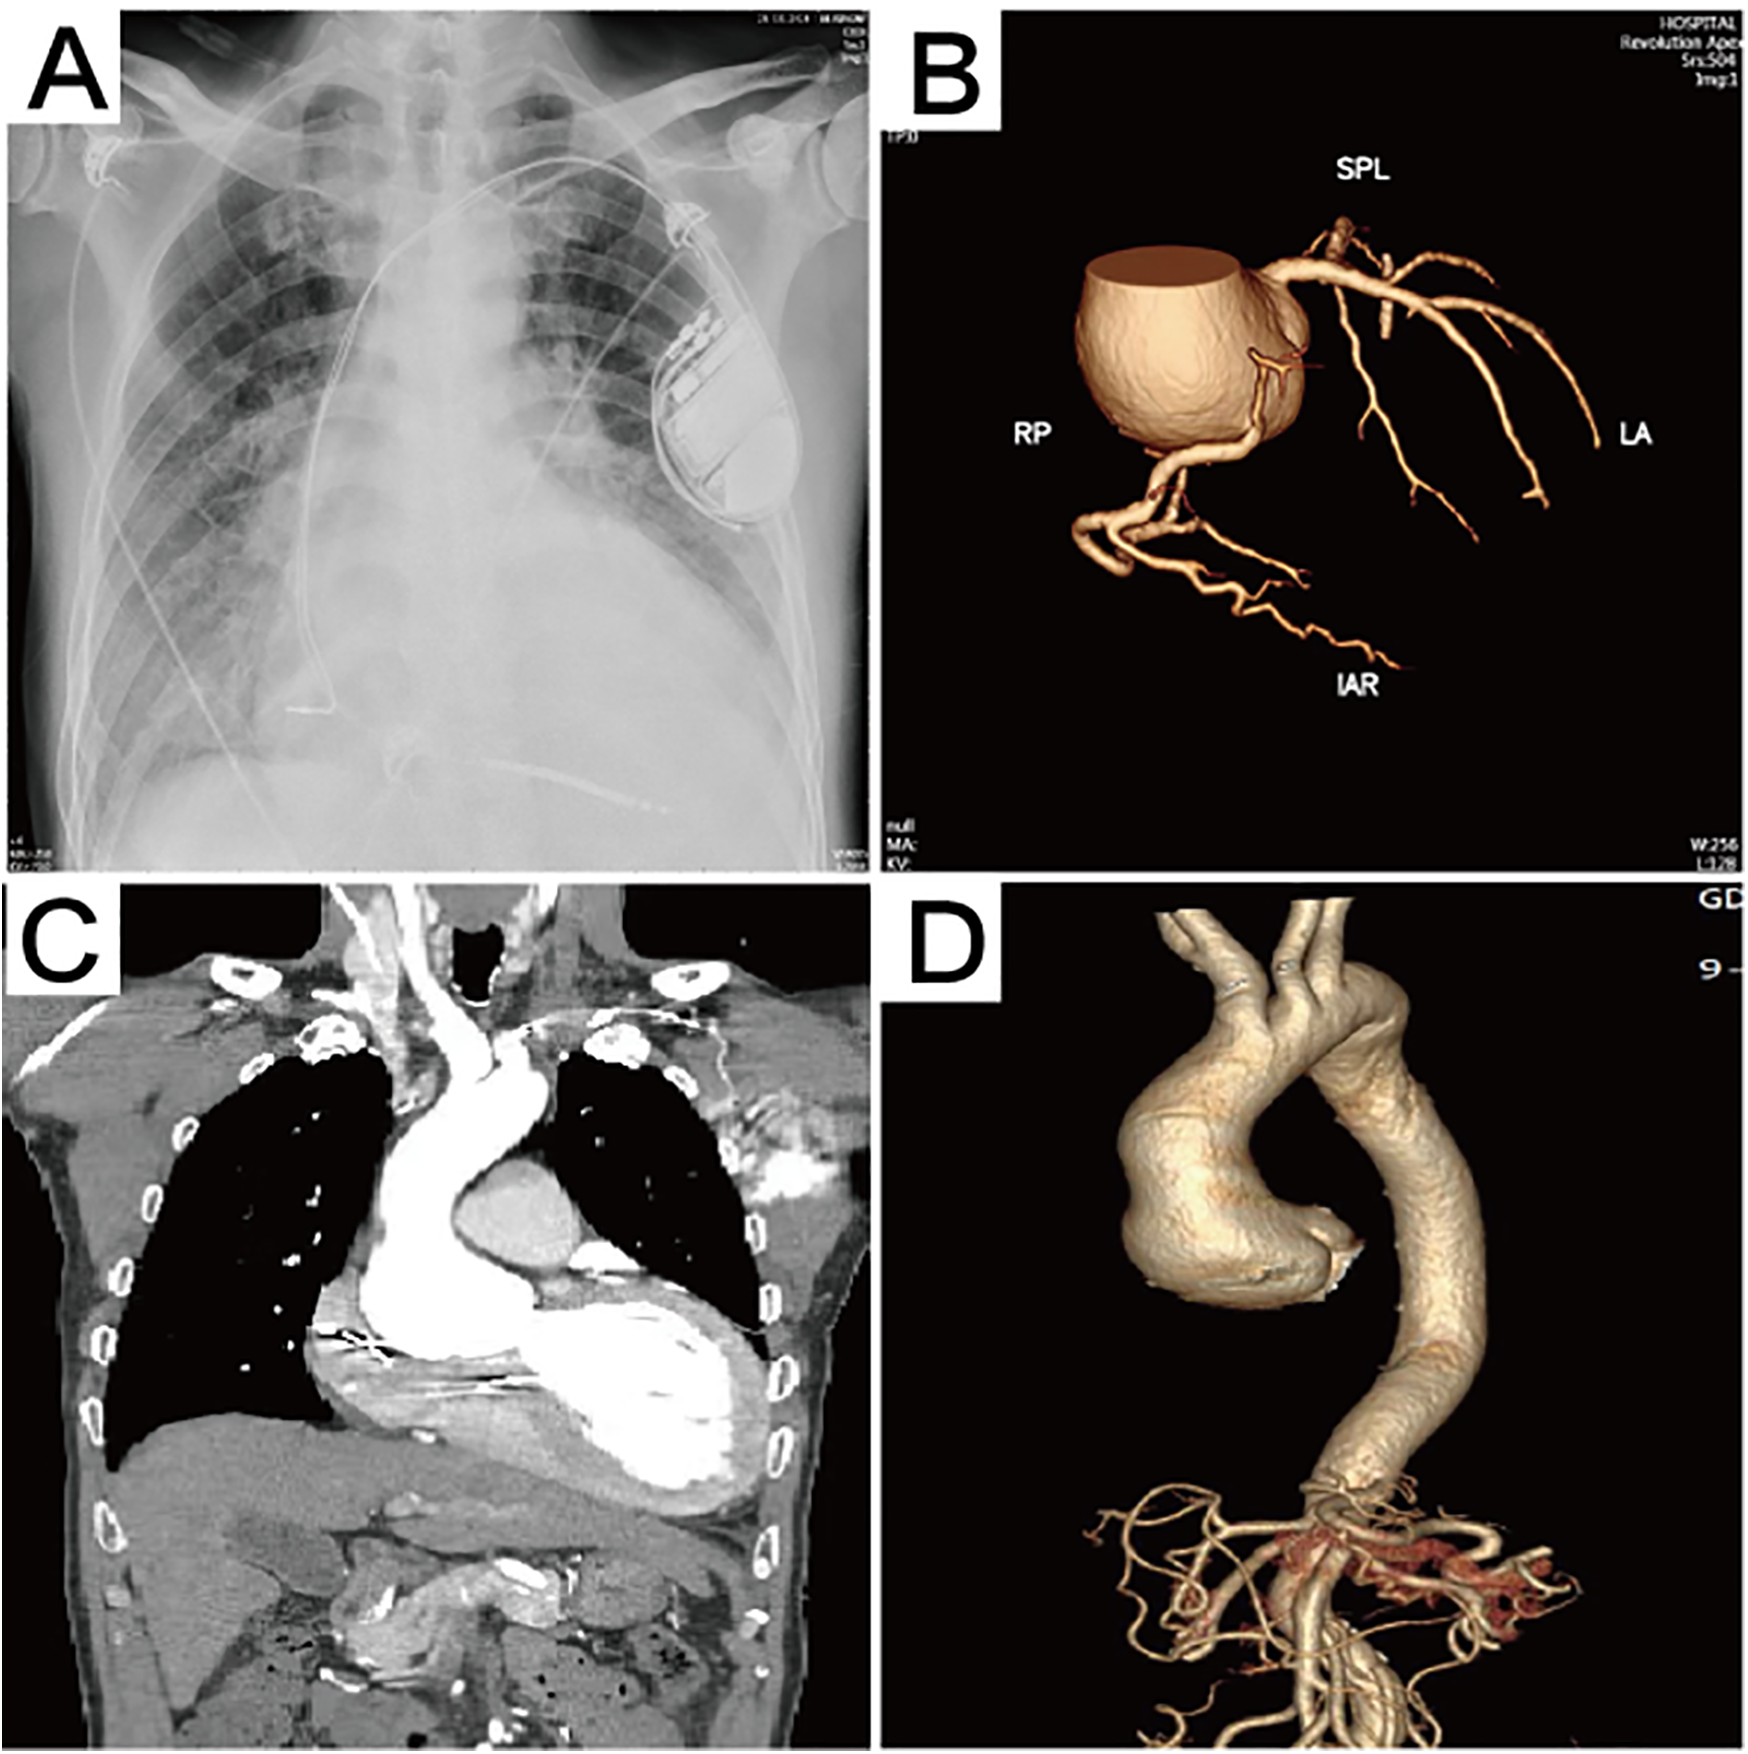

A 60-year-old male patient (weight 60 kg, height 1.70 m, body surface area 1.72 m2) was admitted with a 4-year history of chest tightness and shortness of breath, which had aggravated for 1 month. Four years ago, the patient presented with chest tightness, palpitations, and shortness of breath, which were relieved by rest. The patient did not undergo further diagnostic evaluation or treatment at that time and continued to experience recurrent episodes. In 2023, an implantable cardioverter-defibrillator was implanted due to frequent ventricular premature beats, and the patient was maintained on long-term oral medication, including sacubitril/valsartan, dapagliflozin, bisoprolol, vericiguat, torasemide, and spironolactone. One month ago, these symptoms had worsened and were not relieved by resting. The patient presented with lower extremity edema and fatigue and was observed to sit upright to facilitate breathing. He was subsequently hospitalized in the hospital’s cardiovascular department. The N-terminal pro-brain natriuretic peptide (NT-proBNP) level was 17,245 ng/L, and high-sensitive cardiac troponin (hs-cTnT) level was 0.074 µg/L. Chest x-ray showed pulmonary edema (Figure 1A). He received treatment for heart failure, including cardioprotective theraphy, diuresis to reduce the cardiac load, and other symptomatic treatments. His past medical history was unexceptional.

Figure 1

Preoperative imaging data. (A) The chest x-ray revealed the presence of pulmonary edema. (B) Computed tomography 3D reconstruction of the coronary arteries. (C) Preoperative computed tomography scan showing aortic sinus aneurysm, with the maximum aortic root diameter measuring 53.3 mm. (D) Computed tomography 3D reconstruction of the aorta.

Echocardiography after admission revealed dilated cardiomyopathy, severe aortic regurgitation, mild-to-moderate mitral regurgitation, moderate tricuspid regurgitation, reduced left ventricular systolic function, and general reduction in ventricular wall motion, with an ejection fraction of 22% and a left ventricular end diastolic diameter (LVEDD) of 80 mm. Coronary computed tomographic angiography (CTA) suggested the presence of varying degrees of mild stenosis in all coronary arteries, with no significant lesions identified (Figure 1B). Aortic CTA suggested an aortic root aneurysm, with a maximum aortic diameter of up to 53 mm (Figures 1C,D). Right heart catheterization showed a central venous pressure (CVP) of 3 mmHg, mean pulmonary artery pressure of 29 mmHg, and a total pulmonary resistance of 1.35 Wood units.